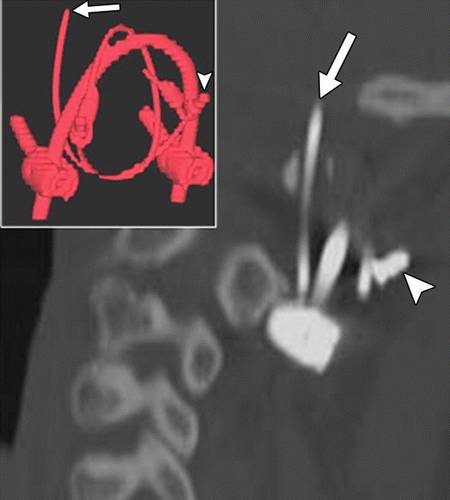

图9A-58岁的女性,颈椎融合手术。侧位X线照片显示结扎线连接器(箭头)分离,并向枕部移位(箭头)。

图9B-58岁的女性,颈椎融合手术,颈椎矢状CT图像和三维CT图像(插图)显示结扎线(箭头)穿入到了枕骨大孔。 颈椎不稳定是这种并发症的另一个后果。 箭头表示连接器。